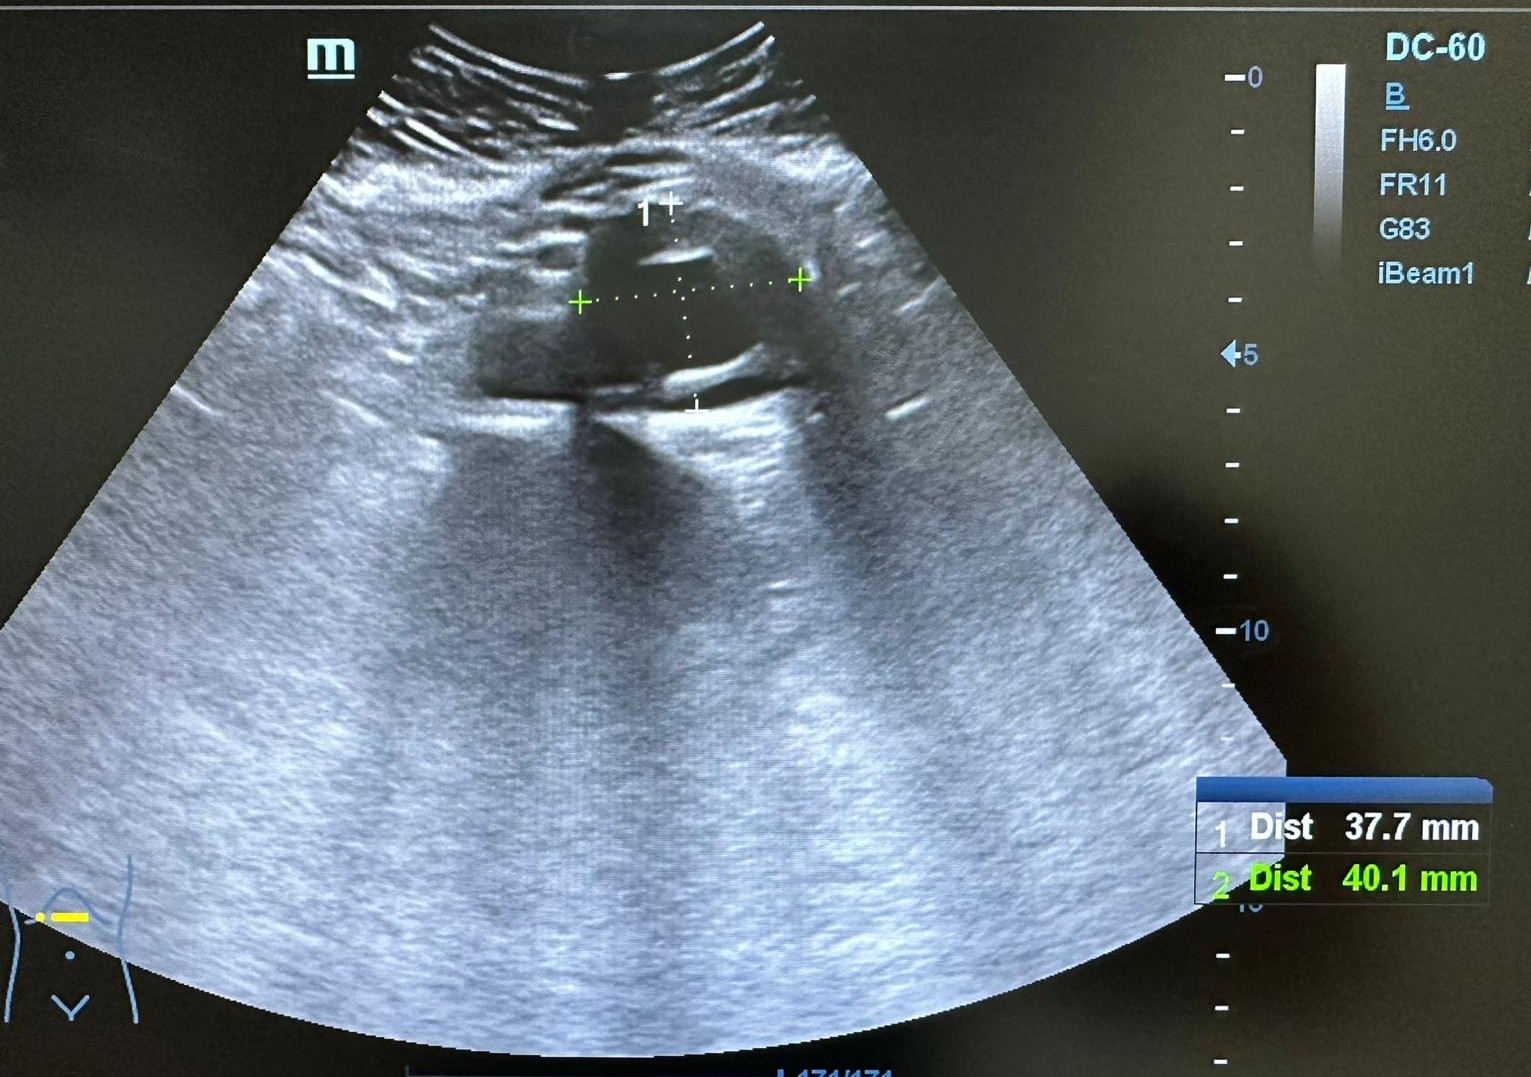

Ecografía clínica AP con los hallazgos siguientes: Presenta dilatación aneurismática de aorta infrarrenal fusiforme con trombo en su interior que disminuye la luz aórtica con diámetro 37,7 x 40,1 mm. Ambos riñones con forma y tamaño normales, buena diferenciación córtico medular sin signos de uropatía obstructiva.